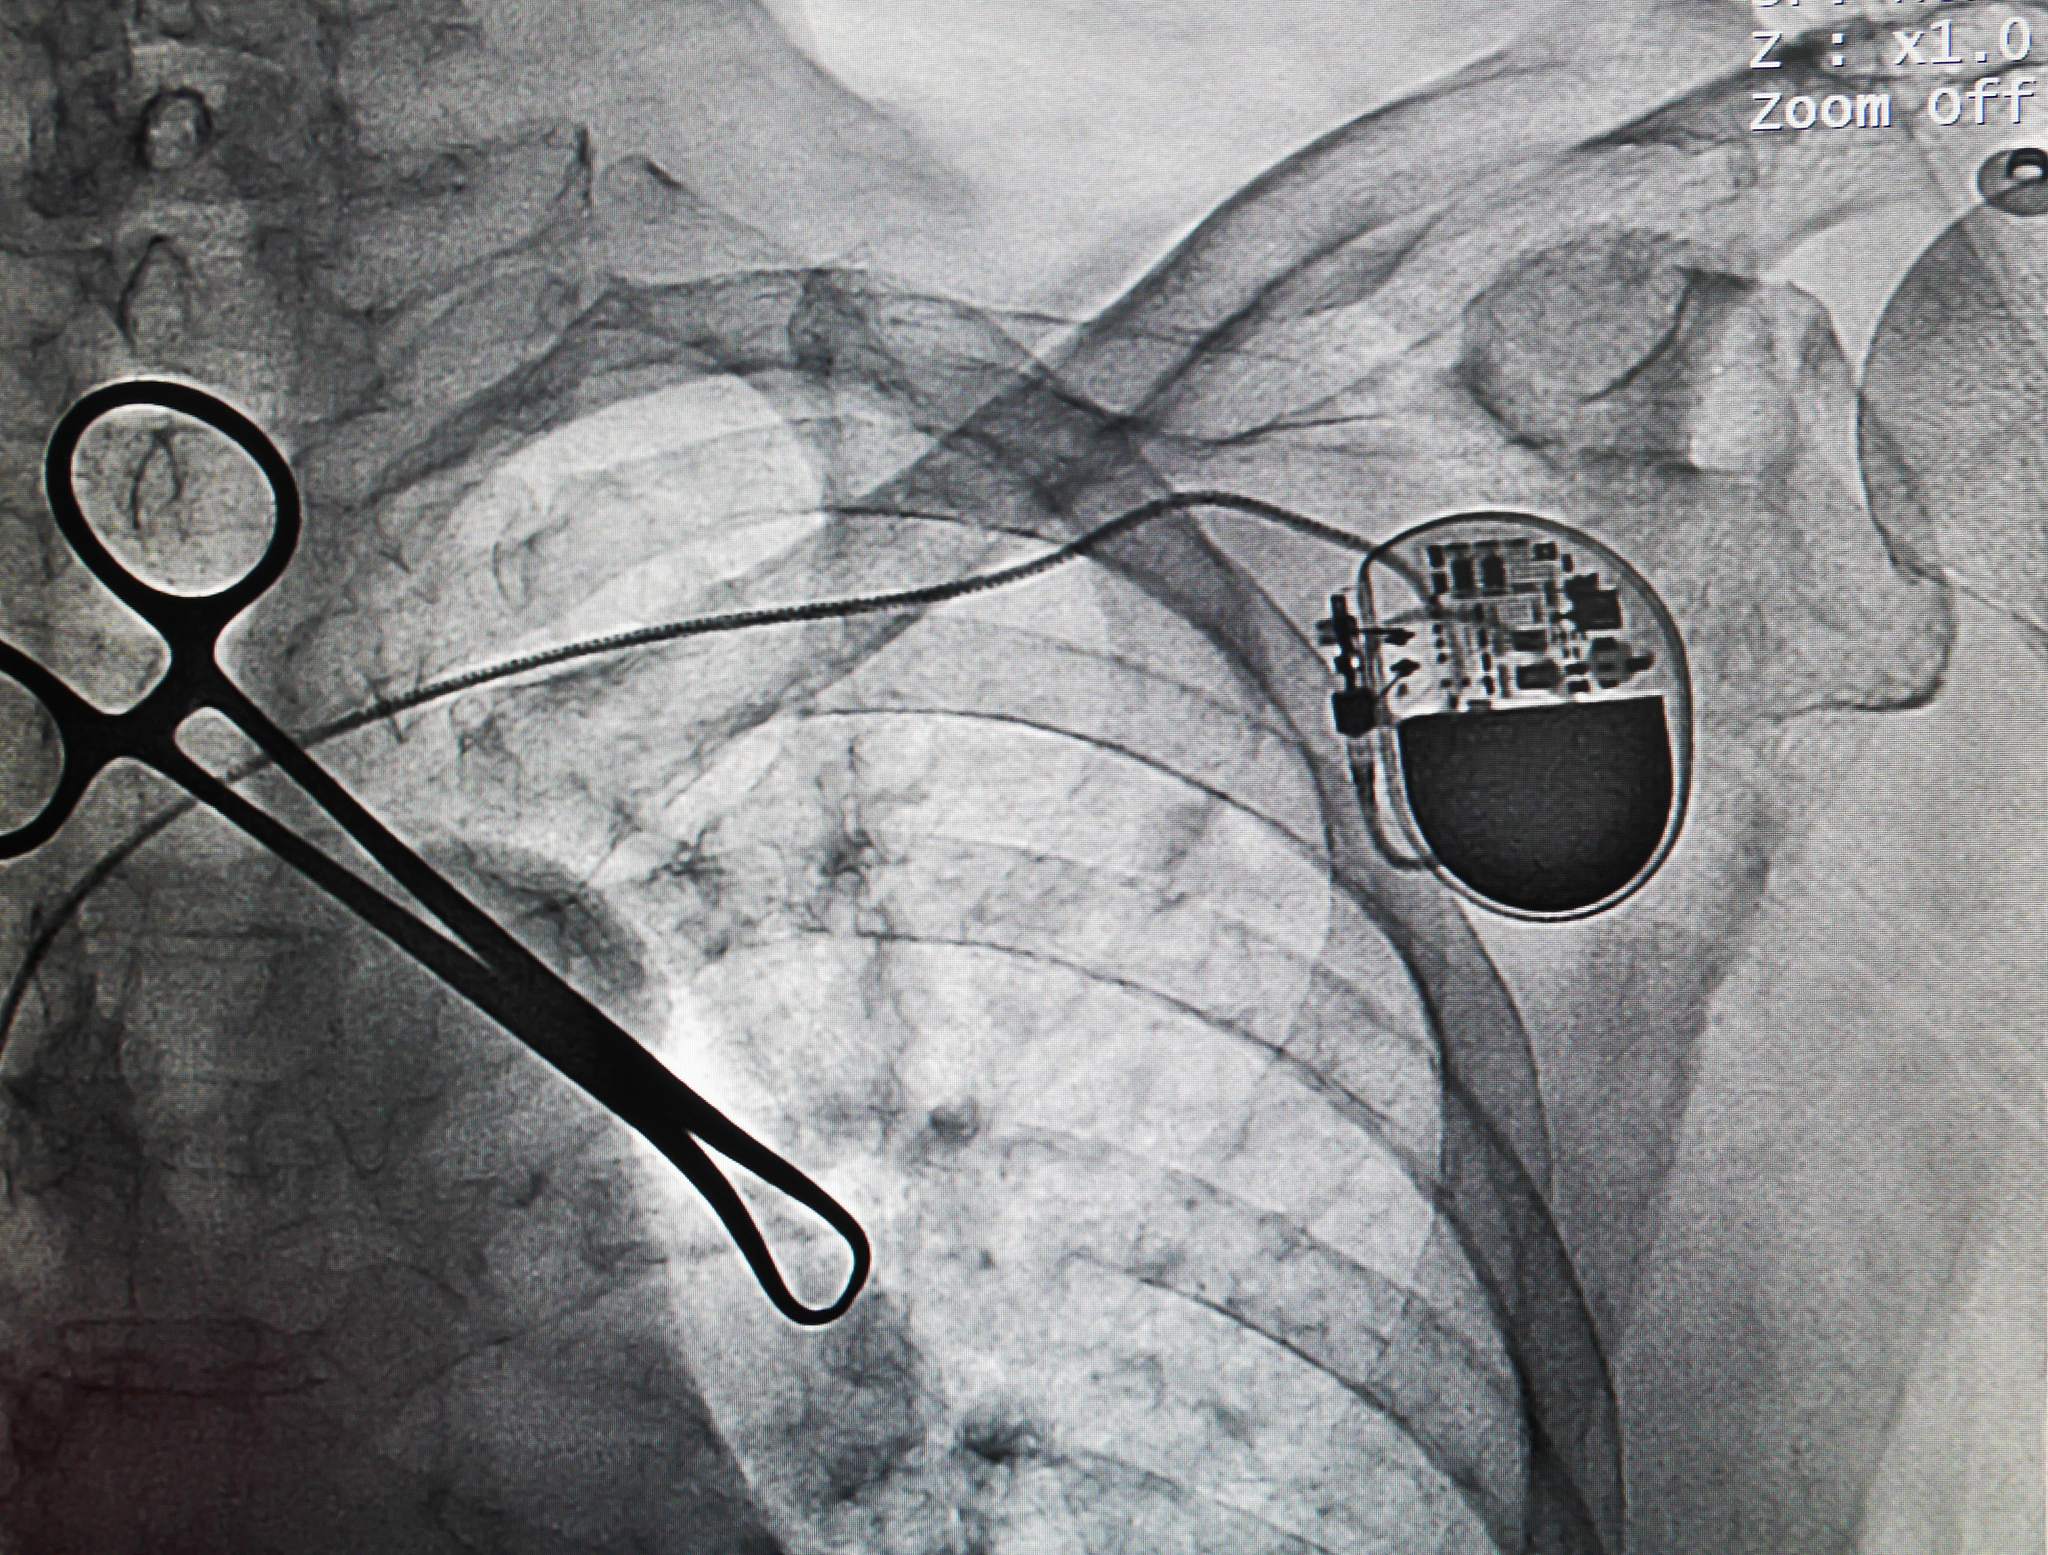

起搏器空窗期

起搏器空窗期是指心脏起搏器在一段时间内无法发出脉冲信号,导致心脏无法被起搏器正常控制的时间段。这通常发生在起搏器电池耗尽或需要更换时,或者在更换起搏器时需要等待新起搏器安装的过程中。在这段时间内,患者的心跳将完全依赖于自身的心律,可能会出现心律失常、晕厥等症状。因此,起搏器空窗期需要引起患者和医生的高度重视,及时采取措施以避免不良后果。